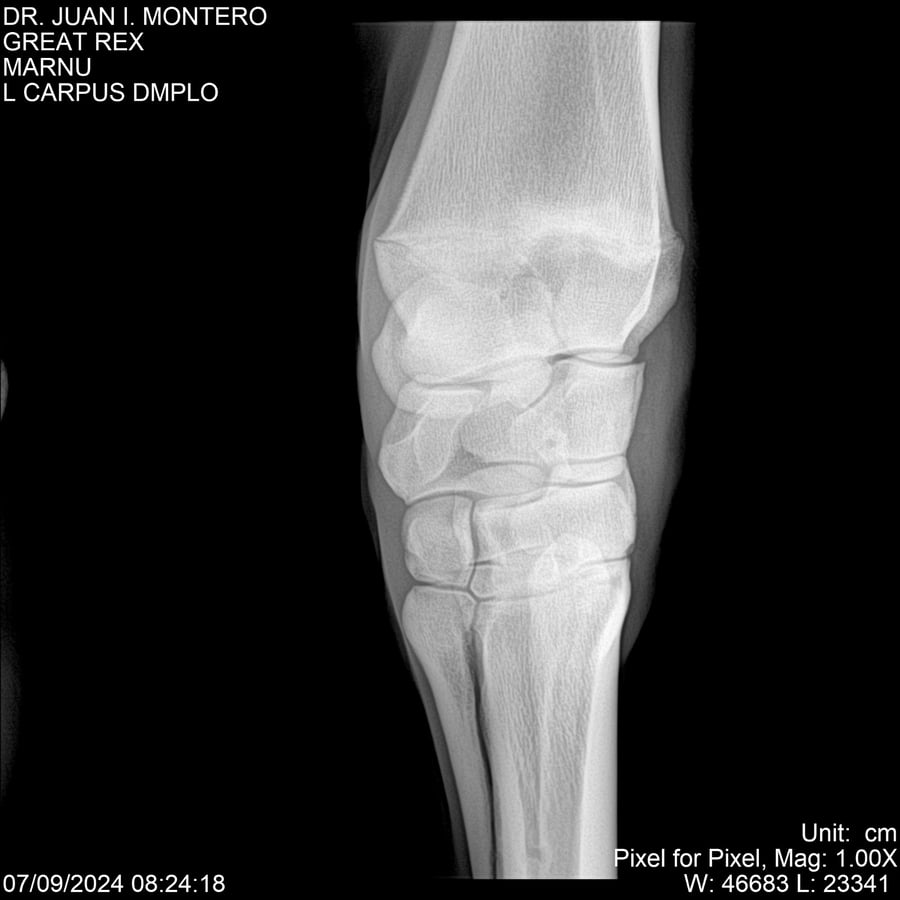

LOTE 4, GREAT REX Lote Anterior Volver al remate Lote Siguiente Ficha Contacto Montevideo - Ficha del Lote Identificador: #282518 Categoría: Yeguarizos Montevideo - 66 Visualizaciones ClicData Contacto Empresa: Abelenda N. R., Walter Hugo Nombre*: Teléfono* : E-mail* : Mensaje Enviar Registrese gratis Este contenido Exclusivo está disponible sólo para usuarios registrados Ingresar